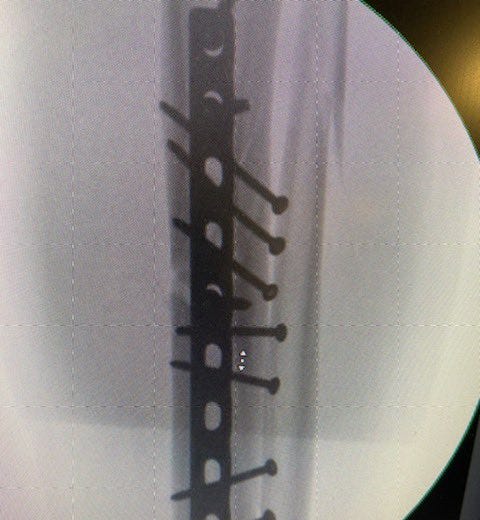

The next morning a long ambulance ride to Central Maine Medical in Lewiston. There a surgeon, a skier himself, amazed by my break – tibia and fibula. “Spectacular,” he called it. “You have strong bones. They resisted the break. When they broke, they exploded.” A spiral fracture splintering into what he called butterfly fragments. “Normally those are three or four millimeters long. Yours were 20. Just amazing.”

Surgery happened in an instant. At least for me, drugged and grateful to be a citizen of the future, of this amazing century with this impossible technology. Here is what he fixed: